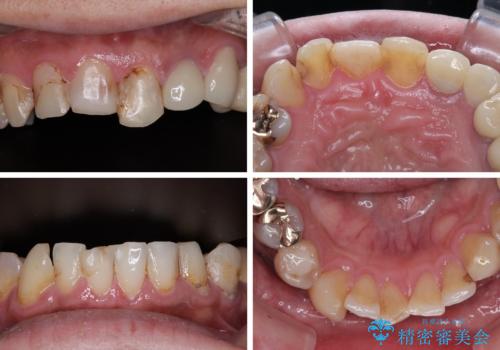

受け口傾向の咬み合わせを治したい 全顎セラミック治療

- すぐに欠けてしまう前歯や、むし歯で全顎的に処置された歯を気にして来院された患者様です。

元来むし歯が多く、さらに受け口傾向の咬み合わせを気にしていらっしゃいました。

当初はむし歯処置が必要な歯のみの治療予定でしたが、捻転や咬み合わせを可及的に改善したいとのことで、全顎的にオールセラミッククラウンにて補綴治療を行うこととしました。